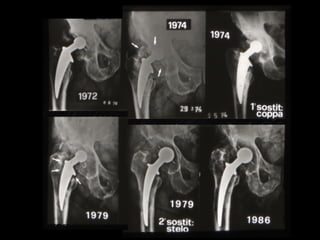

REVISIONI

FINE ANNI 80’

STELO LORD

PROBLEMI

- DOLORE ANTERIORE

di COSCIA

- “STRESS SHIELDING”

IN COMPLESSO, TECNICA

INAFFIDABILE

BOLOGNA 1988